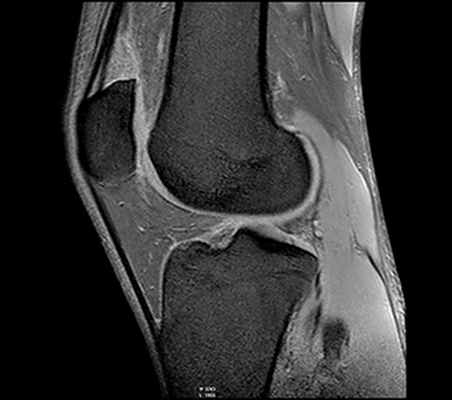

о МР-артрография:

- Позволяет выявлять отек костного мозга и патологические изменения мышц, которые при КТ не визуализируются

• Рекомендации по выбору протокола:

о Рука полностью разогнута в локтевом суставе, супинирована

о Коронарная плоскость: на аксиальной томограмме строится через середину отрезка, соединяющего медиальный и латеральный мыщелки плечевой кости:

- Коронарные срезы: в режиме Т1, а также Т2 с подавлением сигнала от жировой ткани

- Часто полезным оказывается режим GRE

о Аксиальные срезы: в режиме протонной плотности с подавлением сигнала от жировой ткани (PD FS)

о Сагиттальные срезы: в режиме PD FS